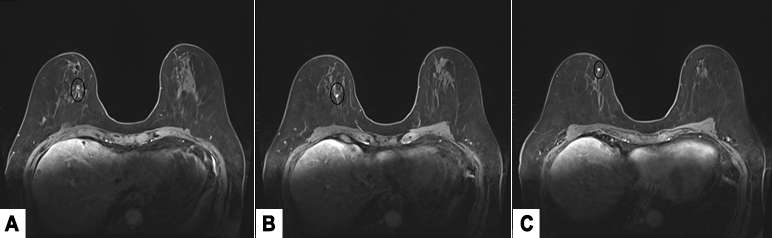

- MRI:

MRI is the most sensitive modality to detect ILC especially for detecting bilateral cancers, with a sensitivity of 93-95%. The most common presentation is a solitary mass with spiculated or irregular margins (95%). Non-mass enhancement is less common (69%)1. On Kinetic imaging, there will be delayed enhancement and less washout in the delayed phase when compared to that of IDC. If a patient has biopsy proven ILC, often the next step is to get an MRI to examine the contralateral breast as ILC is often multifocal and multicentric.